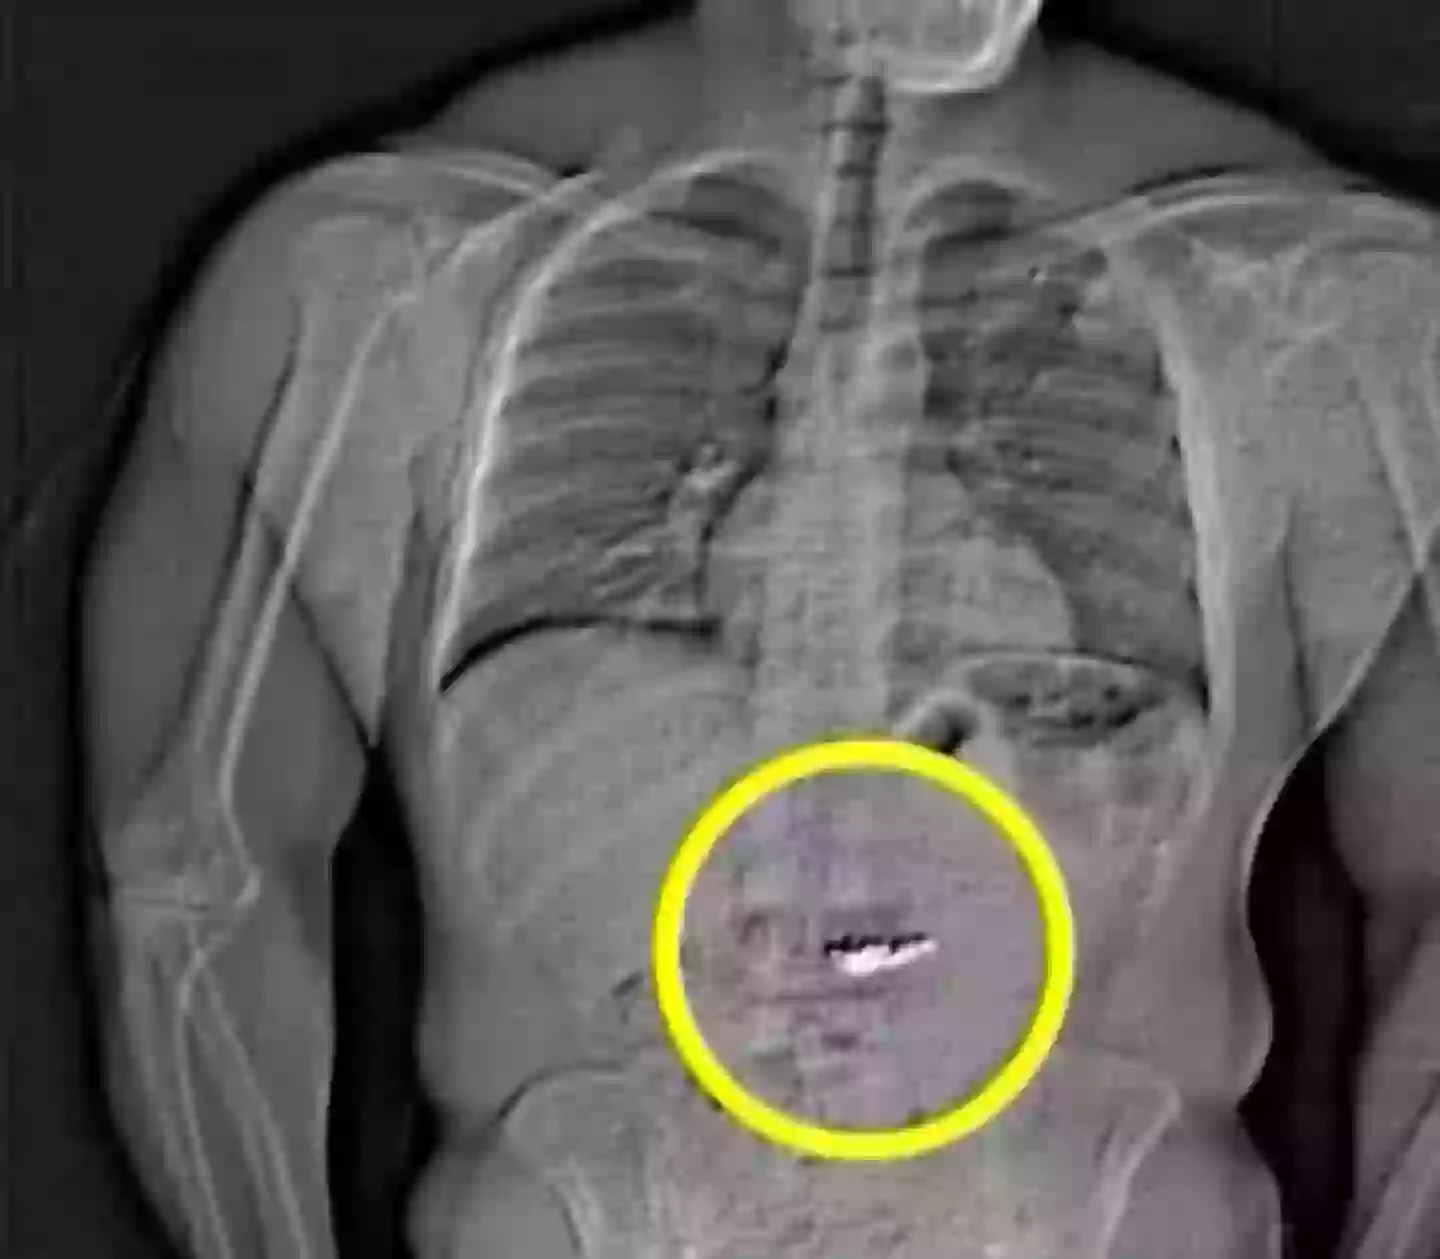

An X-ray of the jewlery found inside Gilder (Fox 35 Orlando)

An X-ray later released by police and taken at the jail showed at least 13 carrats of diamonds allegedly inside Gilder’s stomach, worth just shy of $800,000.

The arrest report said: “These foreign objects are suspected to be the Tiffany & Co earrings taken in the robbery but will need to be collected by WCSO after they are passed through Gilder’s system prior to confirming.”